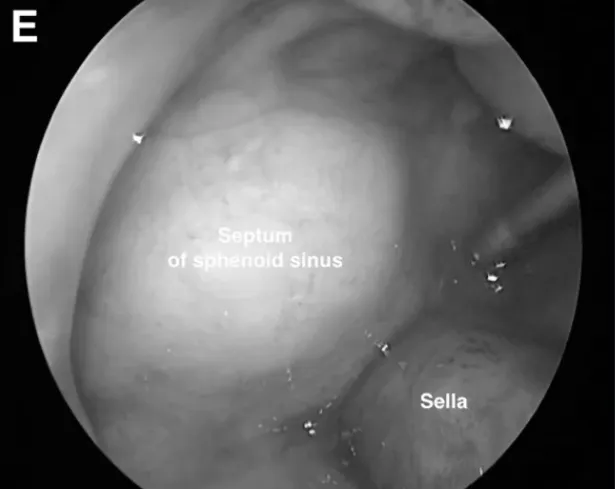

内镜下术中视图显示前内侧三角(AMT)和OPC增大。使用30°角的内窥镜检查蝶窦内是否存有残留的任何肿瘤。

SphS蝶窦的内镜视图。使用颞肌封闭蝶窦SphS,并用明胶海绵和纤维蛋白胶封闭。